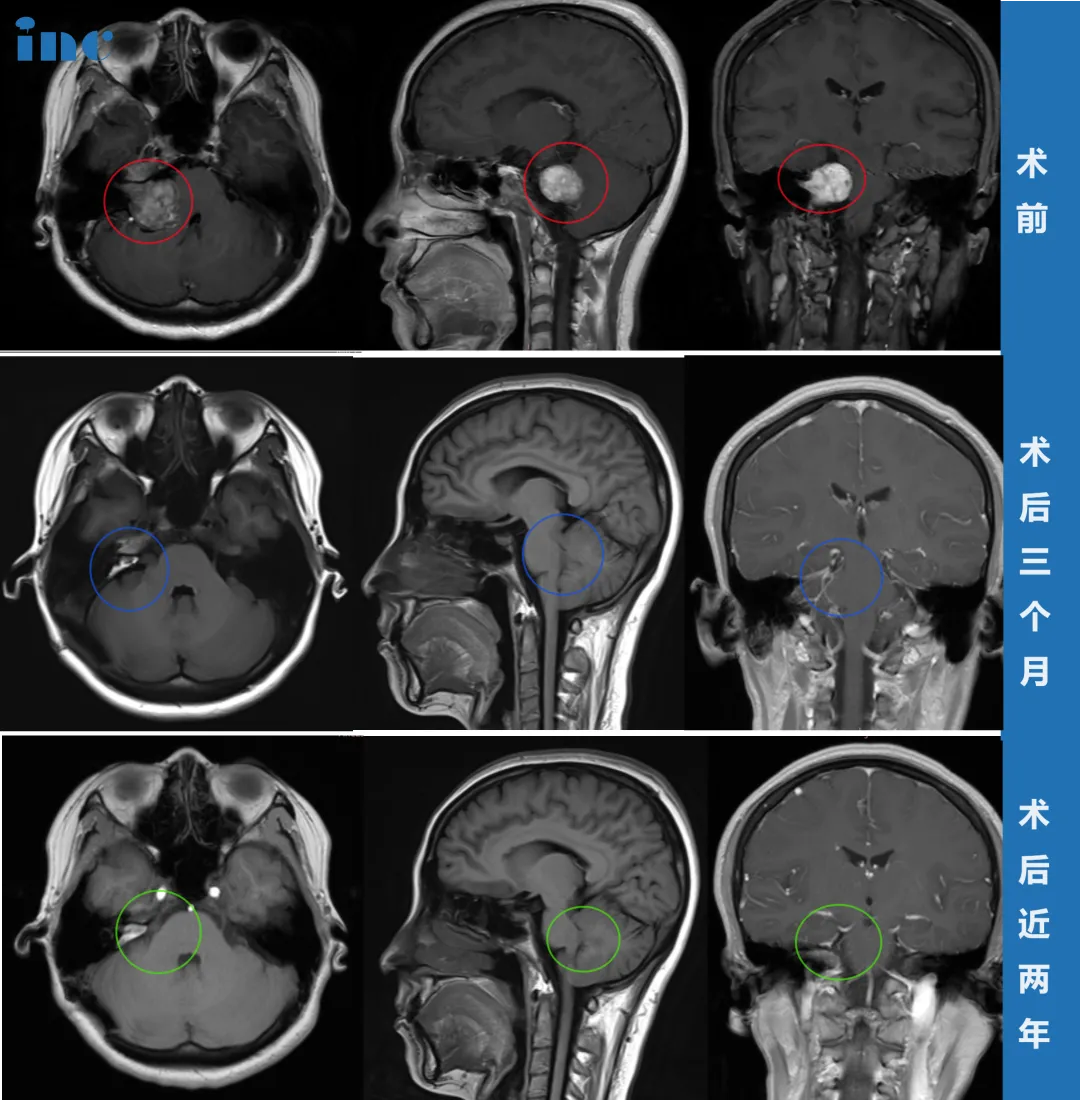

肿瘤巨大,手术是唯一出路。但面对“术后面瘫”的高风险,李女士辗转难眠。在查阅大量资料后,李女士联系上巴教授。手术中,巴教授采用个体化入路,结合神经电生理监测和MRI辅助,在显微镜下将肿瘤完整切除,还为李女士保留了大部分秀发。

术后,李女士恢复顺利。虽因水肿出现过短暂面瘫,但半年后面部功能完全恢复。术后两年复查MRI,肿瘤无任何复发迹象,面部功能良好。